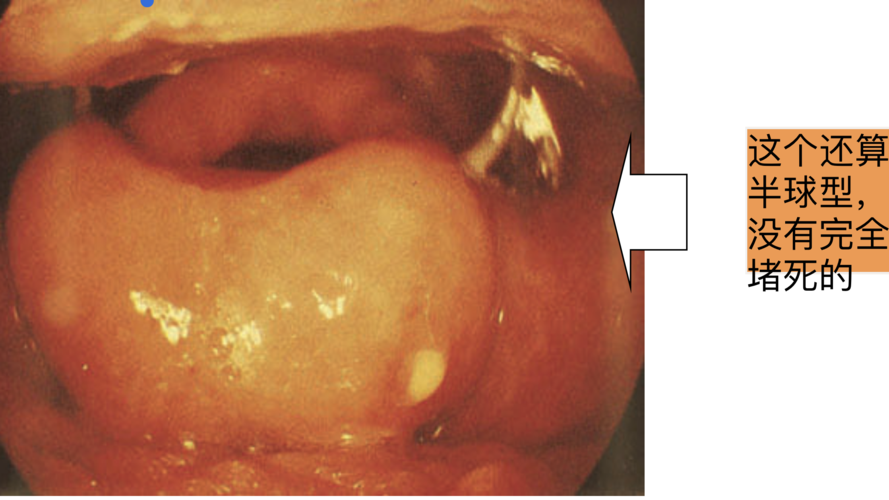

粘膜下血管丰富,易发生水肿e.会厌呈u形或v形

最的凶险咽喉炎之一急性会厌炎

会厌肿大

急性会厌炎喉镜图片

会厌肿大图片